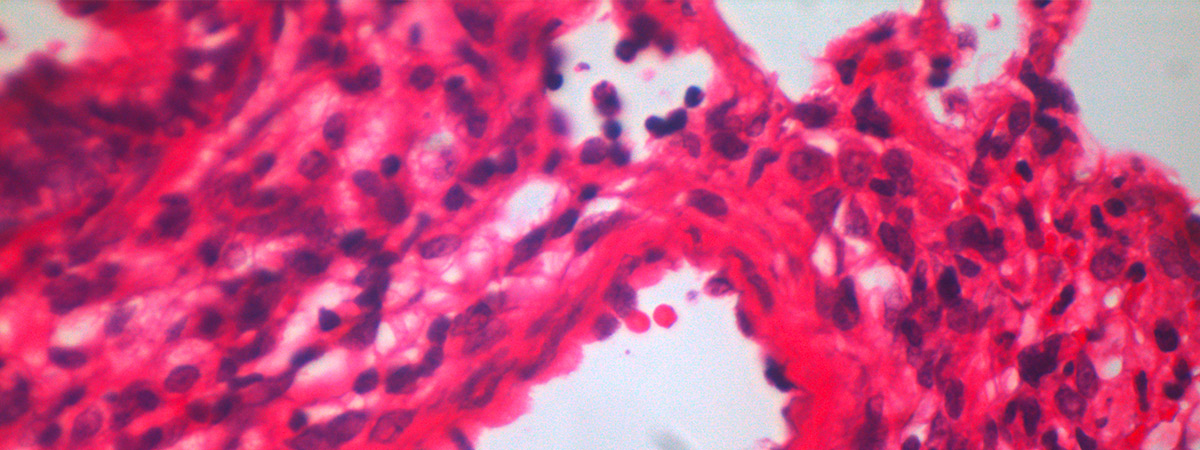

Idiopathic and heritable forms of pulmonary arterial hypertension (PAH) are devastating conditions associated with high morbidity and mortality. The disease is usually diagnosed late by finding a markedly increased pulmonary arterial pressure (increased blood pressure in the arteries of the lungs), the result of progressive narrowing and obliteration of the pulmonary vasculature, which often results in failure of the right ventricle. This disease tends to present in the middle decades of life, with a female predominance.

A major breakthrough in our understanding of the molecular basis of hypertension PAH was the identification of heterozygous germline mutations in the bone morphogenetic protein type II receptor (BMPR-II) in the majority (>70%) of familial cases of the disease and a significant proportion (15-26%) of sporadic cases. Although the presence of mutations in BMPR-II is the greatest risk factor for the development of PAH, it is estimated that only 20% of carriers develop the disease. Additional factors are required for disease manifestation. These may be genetic and/or environmental, though the identity of these factors remains unknown.